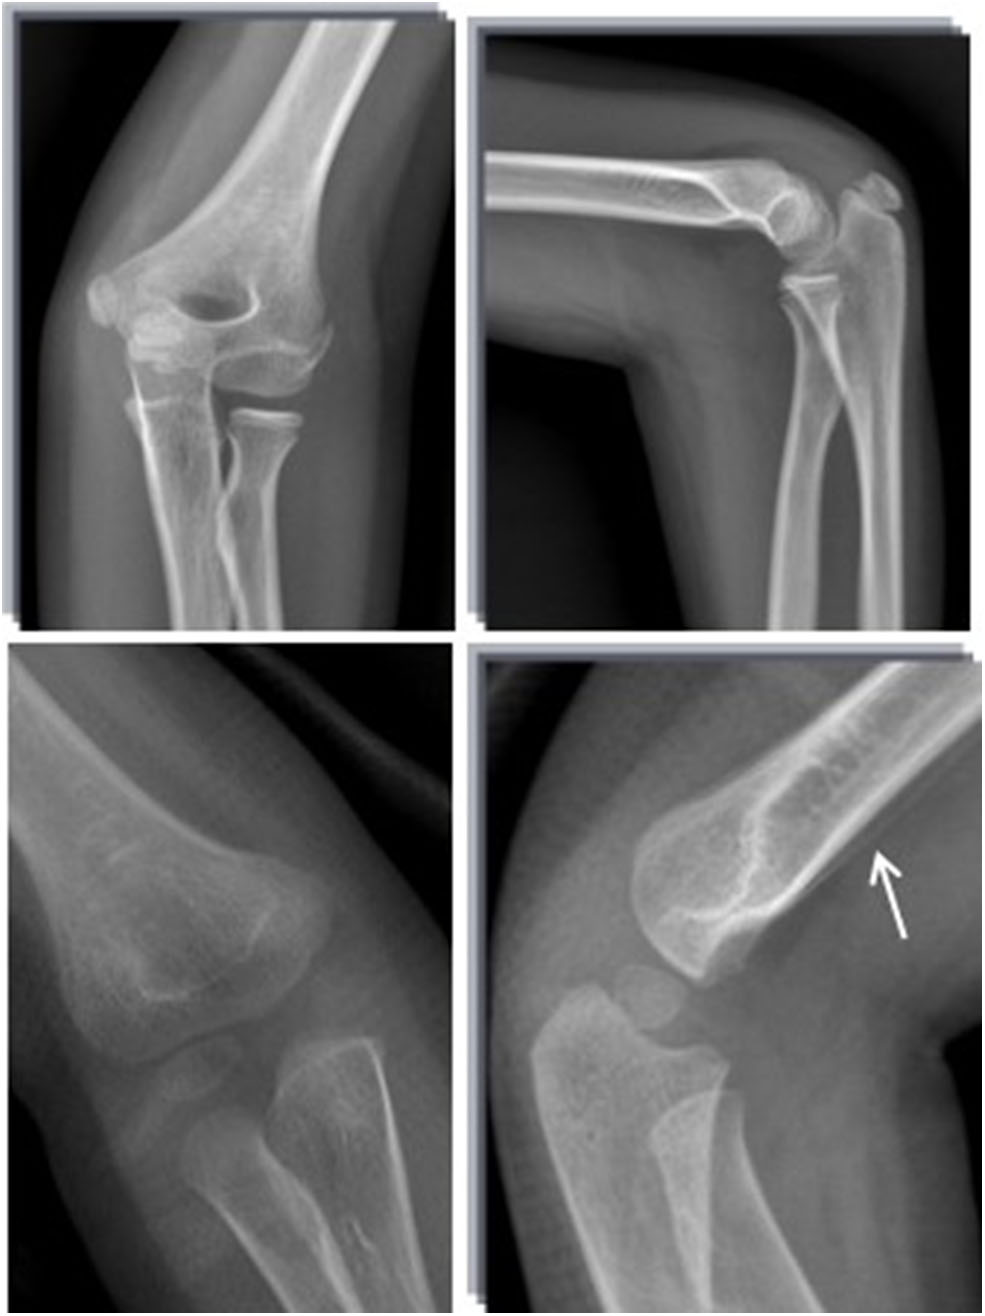

A total of 43,560 pediatric patients with AEI were enrolled, of whom 5,466 patients were diagnosed with fracture, 4,916 of which were confirmed by initial plain radiographs, and 550 were occult fractures confirmed by immediate MRI, immediate CT, or late radiographs 2 weeks post-injury. The mean age of the occult fracture patients was 7.9 years (range 1.6–14 years). The distribution of fractures diagnosed by initial plain radiographs and the distribution and rate of occult fractures in the extremities is summarized in Table 1. The prevalence of occult fractures of the extremities was 10.1% (550/5,466). The history and physical examination findings of all 550 patients led the orthopedic surgeons to suspect a possible fracture although there were no visible signs of fracture on the initial anteroposterior and lateral radiographs. Immediate MRI (n = 193) (Figure 1), immediate CT (n = 199) (Figure 2), or late radiographs (n = 158) (Figure 3) finally confirmed these occult fractures. The physical examination of the 550 patients revealed abnormal soft tissue swelling, persistent pressure pain at the trauma site, and limited active and passive motion because of pain. For patients with distal humerus injury, their anteroposterior and lateral radiographic views showed displacement of the fat pads (fat pad sign) due to joint effusion, which is an indirect sign of fracture (Figure 4).

FIGURE 1

www.frontiersin.org

Figure 1. Standard radiographs in AP and LL projections did not show a fracture. MRI demontrated a fracture in the distal femur (arrow).